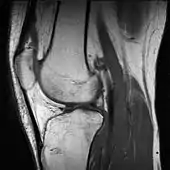

A grayscale MRI of a knee – different gray levels indicate different tissue types, requiring a trained eye.

A pseudocolor MRI of a knee created using three different grayscale scans – tissue types are easier to discern through pseudo color.